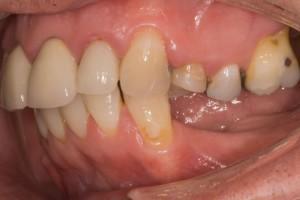

Before implants placement and correction of gum line and ready for implants.